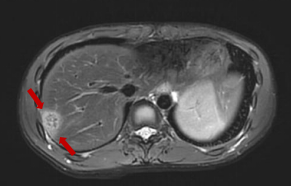

随后,入院查血常规提示嗜酸性粒细胞百分比大于40%,转氨酶明显升高,CT检查提示肝右叶占位性病变。上腹部磁共振增强提示肝右叶包膜下多发液性信号。肥大反应提示丙型副伤寒1:320,考虑沙门菌感染,这是一种由沙门氏菌属细菌引起的常见食源性疾病,可以通过受污染的食物或水传播。

磁共振显示:肝右叶包膜下见多处团片状、楔形病灶。